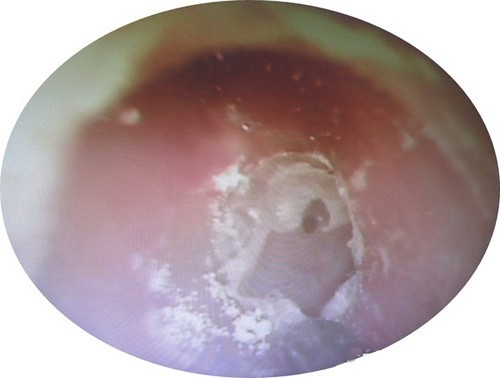

Bệnh nhân chia sẻ, bà có thói quen dùng tăm bông ngoáy tai hàng ngày. Bác sĩ Li Ruiwen chỉ định nội soi tai và kết quả cho thấy trong tai của người bệnh phủ đầy nấm mốc trắng như bông tuyết.

Bác sĩ Li tiến hành lau sạch phần nấm mốc và đã bị sốc khi thấy còn lớp mủ dày phía bên trong và màng nhĩ đã xuất hiện lỗ thủng. Sau 2 tháng điều trị bằng kháng sinh và thuốc chống nấm, tình trạng của bệnh nhân đã được cải thiện rõ rệt.